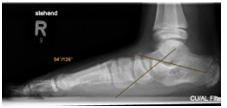

Osteotomie nach Evans und Cotton

Bei Jugendlichen mit fortgeschrittenem Knick-/Senkfuß erfolgt eine knöcherne Verlängerung der Außenseite des Fersenbeins. Dabei wird ein Knochenkeil eingesetzt (Osteotomie nach Evans), so dass auf der Innenseite ein stabiles Fußgewölbe entsteht. In manchen Fällen ist zusätzlich eine Korrektur der Innenseite erforderlich (Osteotomie nach Cotton), ebenfalls kann eine Verlängerung der Wadenmuskulatur notwendig sein (Gastroc Release).

Der Fadenzug erfolgt nach 12-14 Tagen. Verordnungen für Physiotherapie sind meist nicht notwendig, allerdings sind zu Beginn Anwendungen für Lymphdrainage sinnvoll. Die Nachbehandlung erfolgt für 6 Wochen unter Entlastung in einer speziellen Orthese an Stützen. Bis auch längere Gehstrecken ohne Mühen bewältigt werden können, vergehen in der Regel drei, manchmal sechs und in Einzelfällen sogar mehr als neun Monate. Wenn die Kinder im Alltag beschwerdefrei sind, können sie nach Ablauf von zwei bis drei Monaten Fahrrad fahren und schwimmen gehen. Auf Lauf- und Kontaktsportarten sollten die Kinder mindestens sechs Monate verzichten.